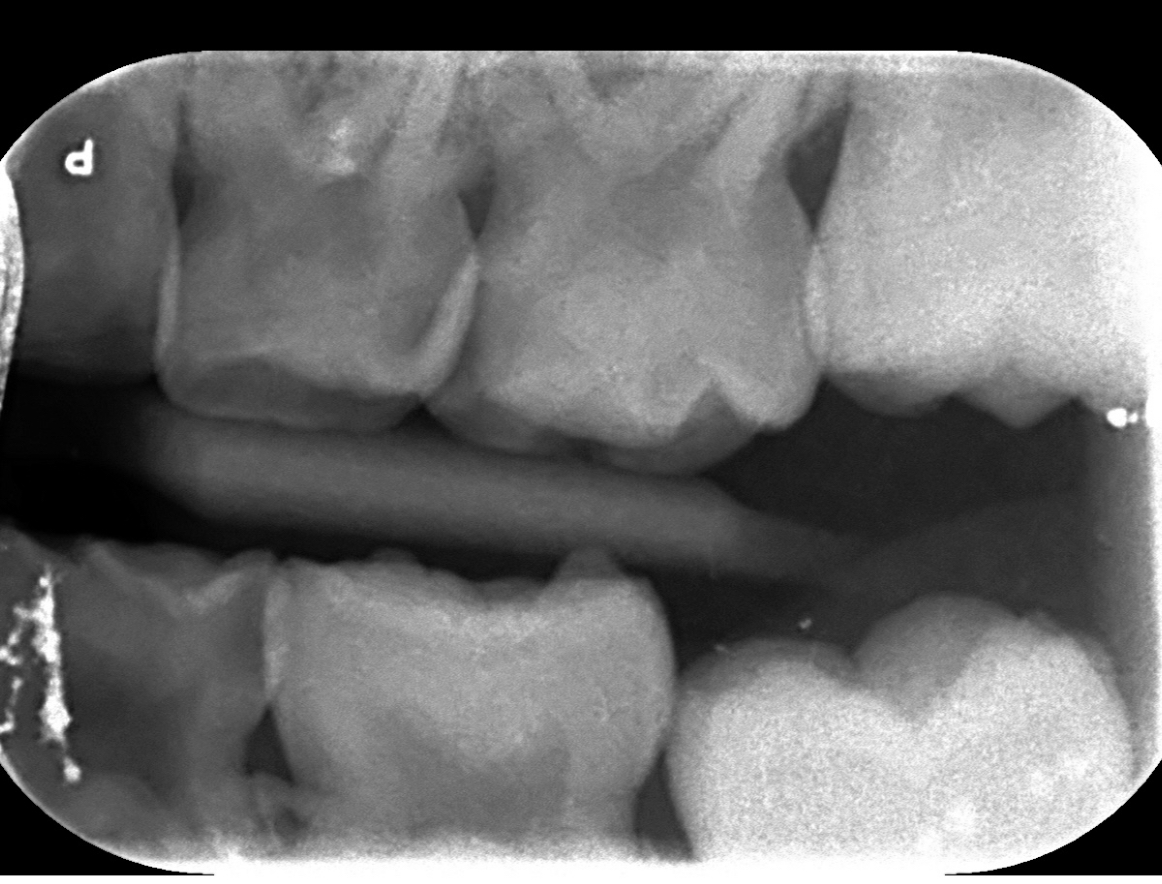

Beste tandartsen, Deze week hebben wij te horen gekregen dat mijn zoontje 3 gaatjes in zijn melkkiesjes heeft. Onze tandarts heeft een voorkeur voor RVS kronen op alle drie de getroffen kiesjes, maar het is ons niet helemaal duidelijk in hoeverre dit is vanwege het effect van de ingreep op een 6 jarige an sich, of de mate waarin de gaatjes gevorderd zijn. Ik zou graag begrijpen welke kiesjes zijn aangedaan en bij welke vullen eventueel mogelijk is (ik zou RVS kronen heel graag willen voorkomen… voornamelijk op de voorste kiesjes die erg goed zichtbaar zijn bij hem). Kunnen jullie dit helpen beoordelen per aangedaan kiesje ahv bijgesloten foto’s? Bedankt!

Ik kan een x-foto normaal in mijn programma bewerken. Deze foto's niet . Maar mogelijk 6 gaatjes die ik gewoon vull, uitgaande v wat ik op de foto zie. Maar pas duidelijk als ik ook in de mond beoordeel.64/65/74/54/55/84.